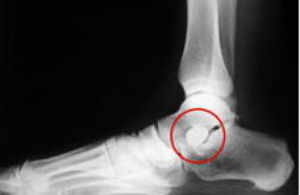

Seno Del Tarso Normal en pie plano flexible

Seno Del Tarso Normal